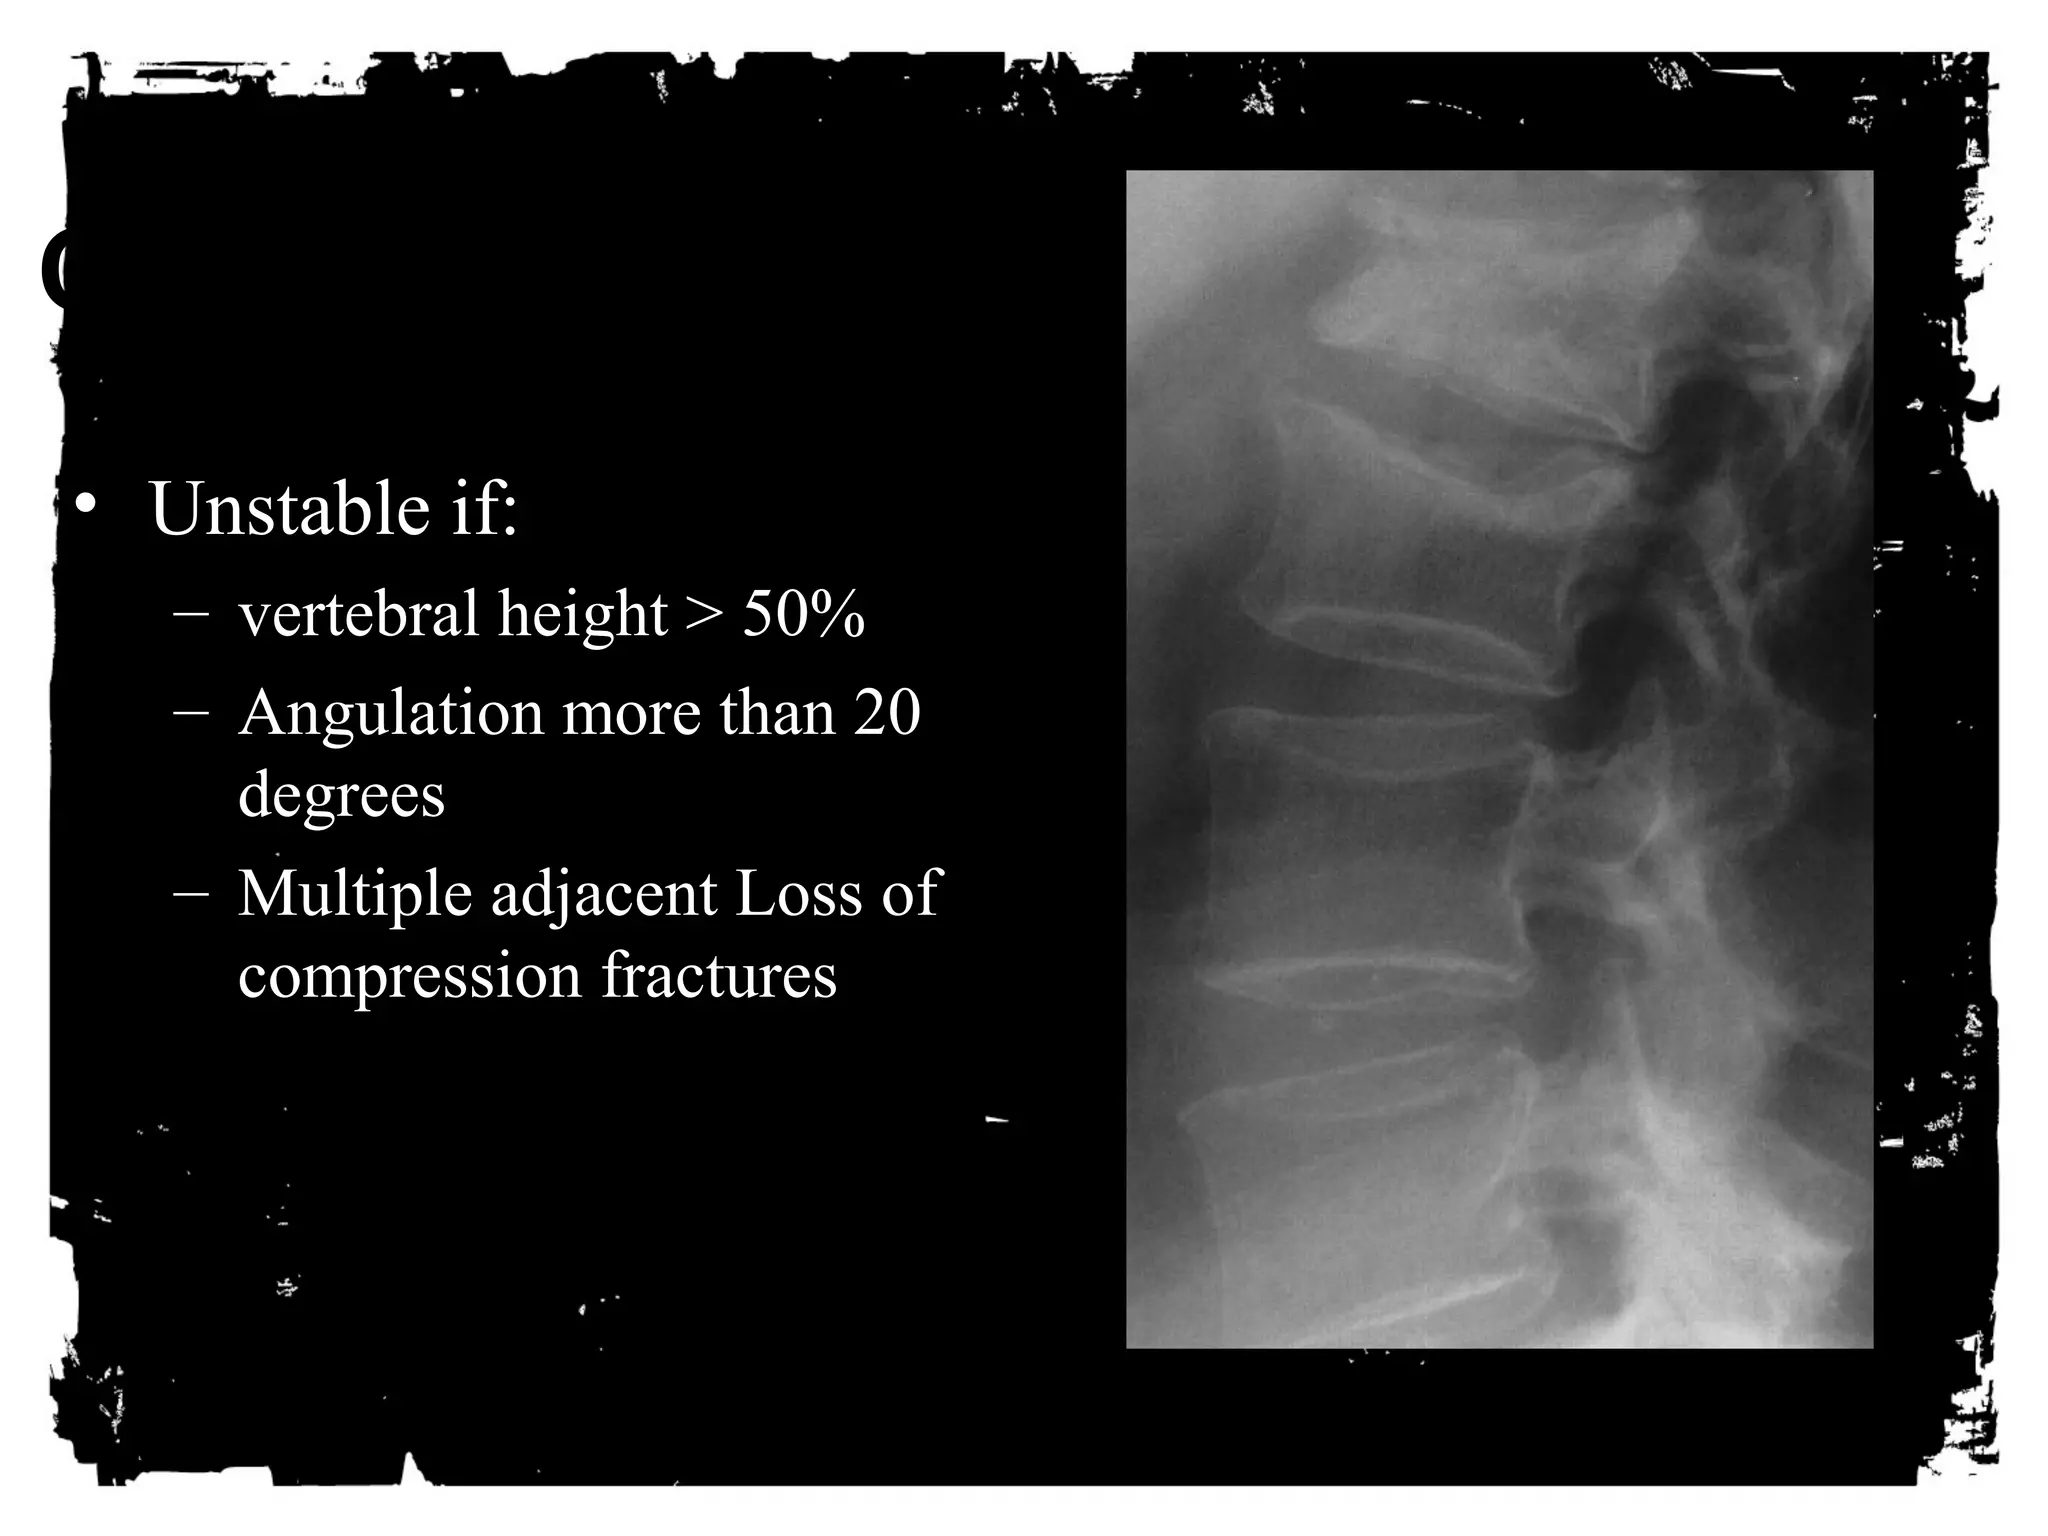

Compression fracture

Injury to anterior column due to anterior or lateral

flexion

Middle and posterior columns remain intact

X-ray - decreased height anterior vertebral body, post

body height normal

Amount of anterior compression usually less than

40% of post body height

Clinically - stable, cord injury rare

CLICK HERE TO ADD TEXT

• Unstable if:

– vertebral height > 50%

– Angulation more than 20

degrees

– Multiple adjacent Loss of

compression fractures